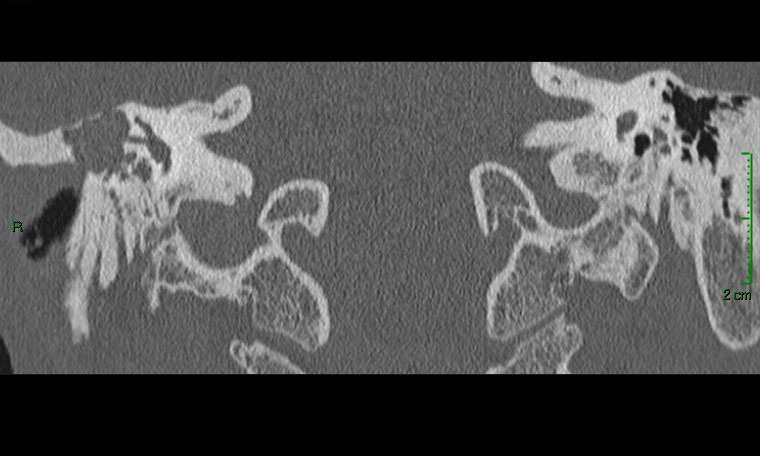

Devant ces atteintes multiples, vous demandez un scanner et une imagerie par résonance magnétique en urgence qui sont représentés ci-dessous.

Question 11 - Qu’en pensez-vous (une ou plusieurs réponses exactes) ?

Question difficile, à laquelle on peut (et doit) répondre avec la clinique. En effet, le canal est ouvert sur le scanner (en coupe coronale sur la figure du milieu), mais surtout on peut le déduire devant le fait que le patient a un nystagmus avec un cholestéatome.

La cavité de l’oreille est noire : donc il y a de l’air. Elle n’est pas comblée par du tissu.

Le scanner montre un comblement aspécifique, sans différencier tissu, liquide ou fibrose.

L’IRM est le seul examen pathognomonique du cholestéatome. Le scanner montre la lyse osseuse mais n’est pas du tout spécifique de l’atteinte. Il n’est pas nécessaire de connaître les structures de l’oreille interne sur le scanner (qui sont très compliquées), mais il faut au moins reconnaître une oreille moyenne pleine (contenu gris) d’une oreille saine aérée (contenu en noir). On peut ensuite déduire de l’énoncé les destructions correspondantes. On aurait pu aussi dire dans cette question que le canal du nerf facial était détruit : c’est forcément le cas puisqu’il y a une atteinte du facial.